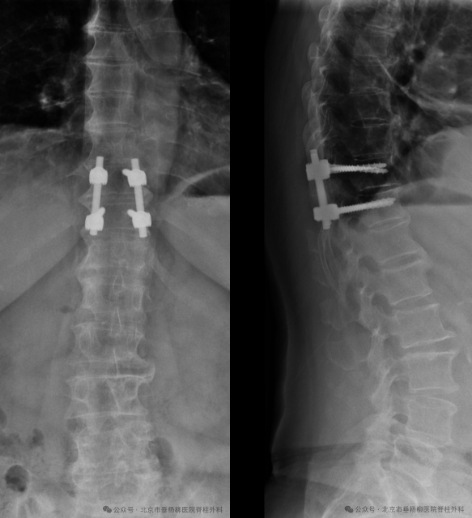

进一步完善术前检查,除外手术禁忌症后,骨四科(脊柱外科)的姜树东主任及唐新力医生给患者在全麻下做了后路胸椎椎板切除减压病灶切除椎弓根钉内固定术。术中医生小心翼翼的剥离,将肿瘤完整取出。手术十分顺利,未损伤到胸膜、脊髓、肋间神经、肋间动/静脉血管等重要解剖结构。手术采用微创小切口短节段固定,减少了对病人的手术创伤,缩短了术后愈合的时间。

术后复查CT提示肿物已被全部取出。

钛合金内固定物位置良好。

术后患者第2天即感疼痛消失,术后5日患者顺利出院。